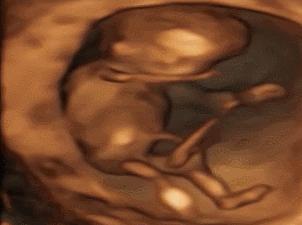

其实小家伙很小的时候就已经开始“闹腾”了:妥妥的一个运动健将!

小碎步向前缩,撅着小屁股用力一蹬,身体向后滑去——“母胎版蛙泳”动作很标准嘛!

不行,刚才的动作不够标准,再来一次!

不过,力气好像还是太小了,算了,休息休息再说~